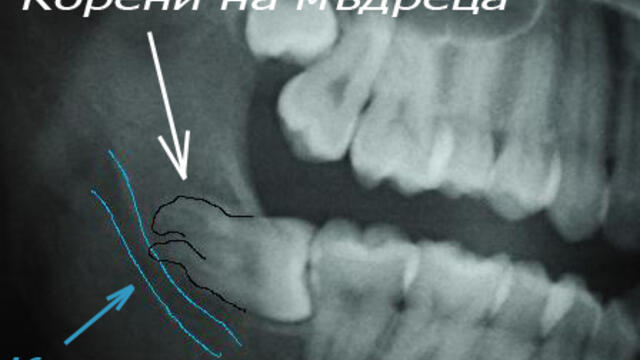

Откриване и изваждане на ретиниран мъдрец! Extraction of horizontal Lt. Mn third molar - Videoclip.bg

Гледай Откриване и изваждане на ретиниран мъдрец! Extraction of horizontal Lt. Mn third molar, видео качено от mentos, във Videoclip.bg - видео споделяне за всички българи!